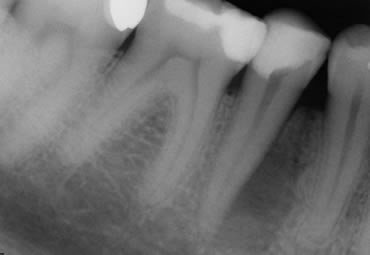

Large Perio-endo lesion, before treatment, during treatment and at 18 month follow up